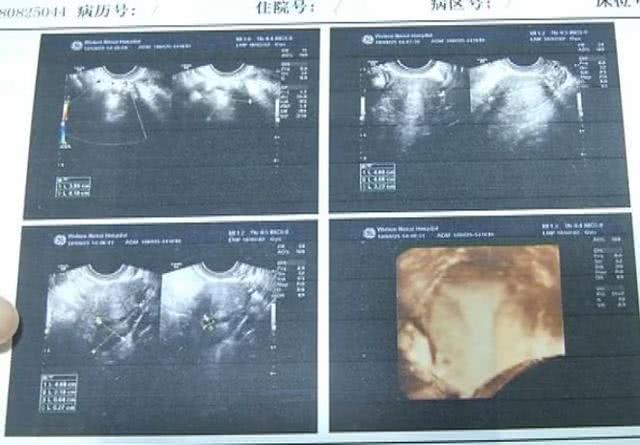

随着年龄增大,小张也到了谈婚论嫁的年纪了,婚期就定在今年底。考虑到婚后要怀孕生小孩,于是,前两天,小张在男友的陪伴下来到武汉做体检。结果B超显示,小张的左侧卵巢呈多囊样改变,右侧附件区有混合性包块。医生表示:“她除了有多囊卵巢综合症,并且还有畸胎瘤……”